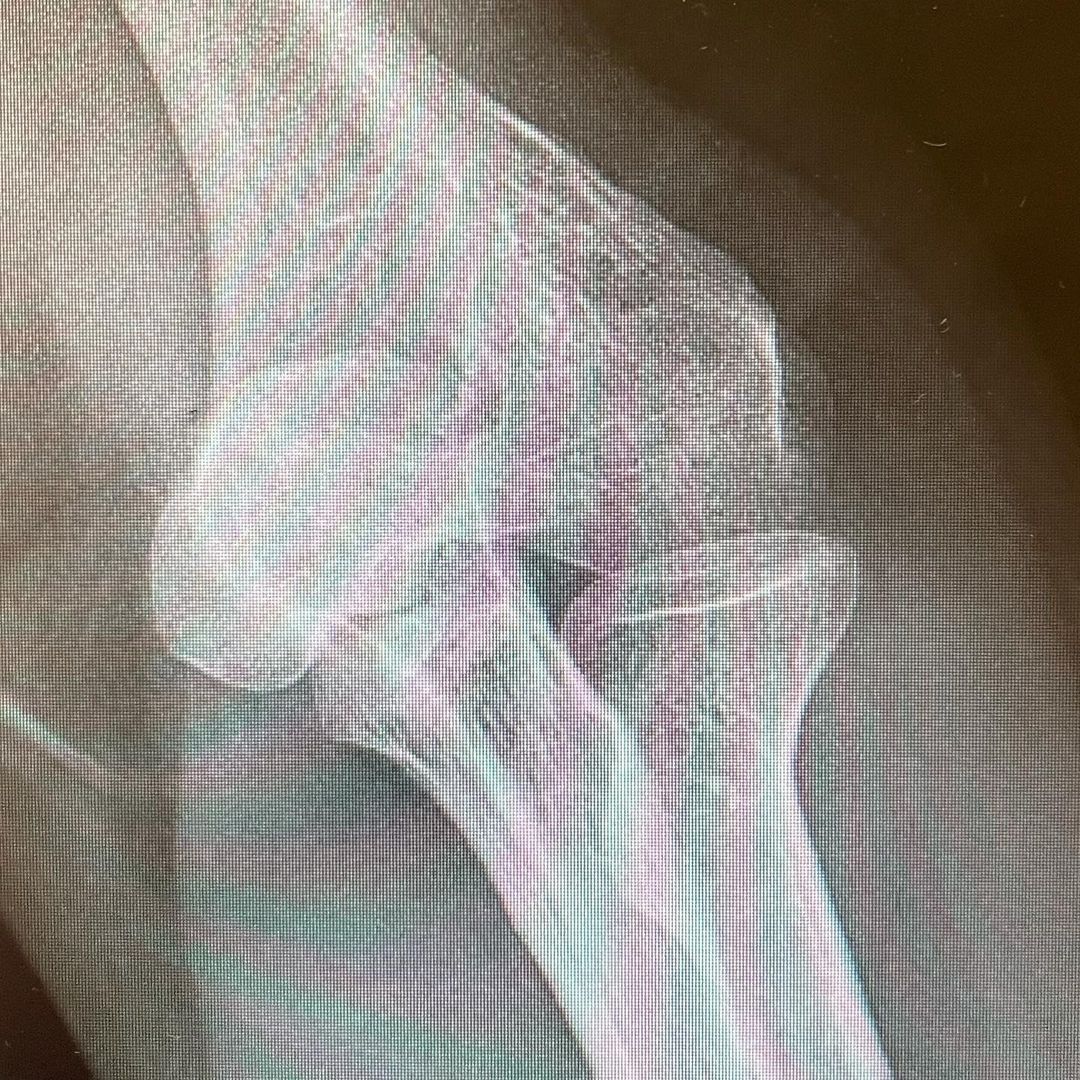

Bill shared his ex-ray on Instagram revealing that he fell and broke his elbow

The 45-year-old took to Instagram to share his x-rays after a nasty fall caused him to break his elbow.

“This image probably has a few things wrong in it courtesy of my dysplasia… but can you find the most recent traumatic damage? Have a super weekend everyone! And get vaccinated